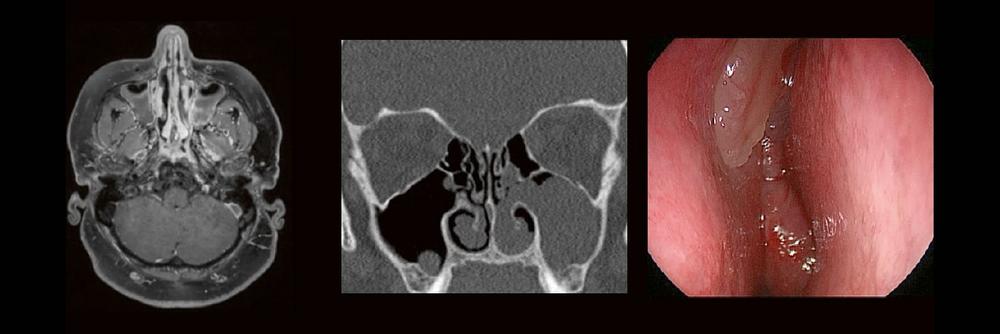

HNO & Radiologie: gemeinsam durch die NNH – ein Joint Venture (Webinar | Online)

Dr. med. André ReisbergDr. med Sebastian Plößl Die bildgebende HNO-Diagnostik macht es Anfängern nicht leicht. Die Anatomie ist komplex und weniger intuitiv als in anderen […]